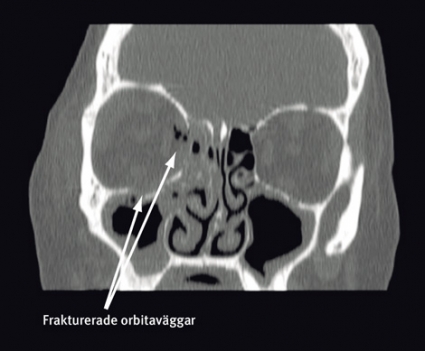

Noggrann klinisk undersökning är av största betydelse i utredningen och en förutsättning för att upptäcka och bedöma de olika komplikationerna, såsom fastklämd extraokulär muskulatur, bulbskada eller synnervsskada. Vid misstanke om fraktur ska ansiktsskelettet undersökas med datortomografi med tunna axiala snitt, och från de axiala snitten görs koronara och sagittala reformaterade serier. Avbildning av ögonhålan i dessa tre plan är nödvändig för diagnostik av orbitaväggsskador och för planering av rekonstruktionen. Tredimensionella bilder ger framför allt en bra visualisering av ansiktsfrakturer utanför orbitan och av implantat vid postoperativa undersökningar.

En 53-årig kvinna föll ner för en trappa, slog sig i ansiktet och ådrog sig högersidiga orbitafrakturer. Preoperativt fanns inget dubbelseende eller enoftalmus, däremot smärta i ögat vid blickriktning uppåt och lateralt. Preoperativ datortomografi visade en ren blow-out-fraktur av orbitabotten och medialväggen (Figur 2). Defekterna involverade större delen av orbitabotten ända bak till orbitans apex samt den mediala orbitaväggen upp till sutura frontoethmoidalis. Volymbestämning gjordes i mjukvaran Osirix efter att orbitans begränsningar markerats på alla axiala snitt mellan orbitans övre och nedre begränsning (60 snitt). Den skadade sidan uppmättes till 31,3 cm3, att jämföra med den friska sidans 26,0 cm3.